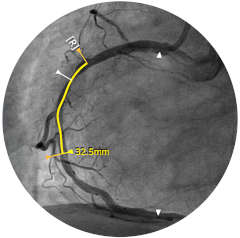

Figura 1

Construida sobre una plataforma inteligente basada en aplicaciones que puede escalar para satisfacer las necesidades cambiantes de su laboratorio cuando se disponga de nuevas aplicaciones o modalidades, sin necesidad de adquirir nuevo hardware. Solo Philips IntraSight ofrece las mejores herramientas de imagenología y fisiología de su clase con iFR, corregistro iFR*, FFR, IVUS, corregistro IVUS* y Angio+*. Con su arquitectura modular, IntraSight se mantiene a la vanguardia de los últimos avances y actualizaciones de seguridad importantes.

Presentamos la nueva plataforma de aplicaciones intervencionistas Philips IntraSight, en la que la imagen, la fisiología, el corregistro* y el software se unen para facilitar una atención óptima del paciente. IntraSight ofrece un conjunto completo de modalidades clínicamente probadas, como la iFR/FFR, la IVUS y el corregistro* para simplificar las intervenciones complejas, acelerar los procedimientos rutinarios y proporcionar una mejor atención al paciente.